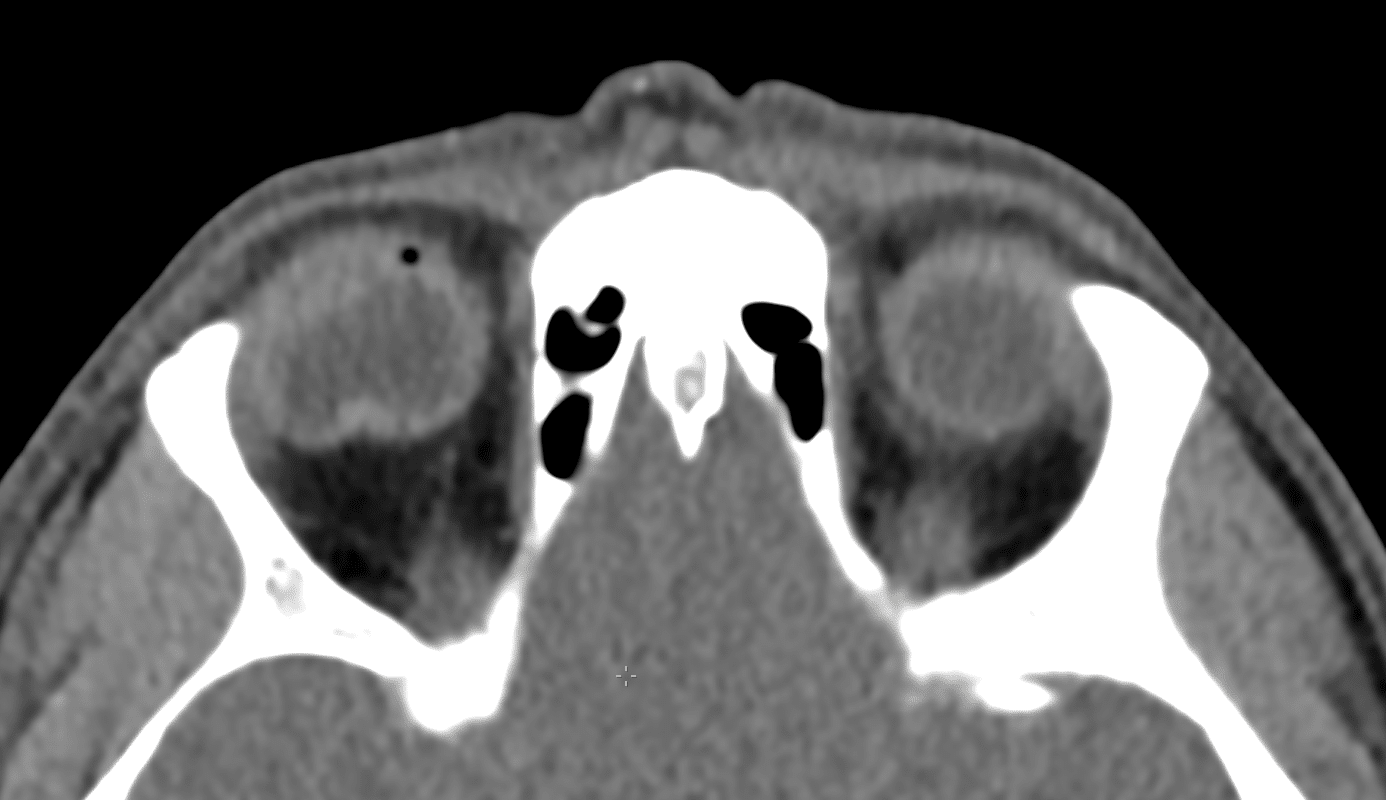

CT Case 020 • LITFL • CT scan interpretation